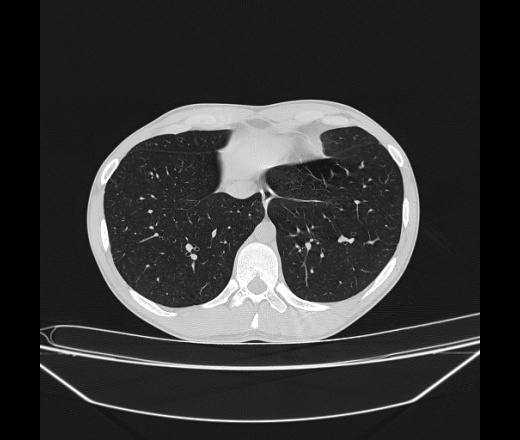

Молодой парень 18 лет, призывник, при прохождении ФЛС на верхушек левого легкого выявили очаги средней интснисвности с нечеткими контурами, тяжи. Сделали бок и томограммы 6-7-8. Везде описывают как очаговый твс. Вижу только перибронхиальный фиброз. Что за изменения в бронхах, указано нижи стрелками, тоже перибронхиальный?

Не стал бы говорить об очагах. Акцентировал бы не на фиброзе, а на тракционных бронхоэктазах. Не обязательно они результат tbc бронхов, но проверить не помешает.

Иван, пациент ведь уже "направлен с ОПТД", так?surprise Возвращайте его назад с заключением о возможном микобактериозе. Остаточные поствоспалительные ( посттуберкулёзные?) в дифряд.Очаговый твс с неясной активностью они уже себе "нарисовали", как я поняла.

+1 за микобактериоз.